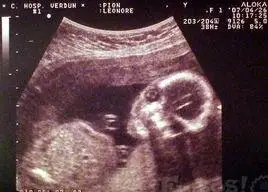

b超照

相关图片

孕30周b超产检宝宝头偏小,医生安慰:女生头小说明脸小更漂亮!

眼看着孕期已经3个月,但b超检查却怎么也找不到子宫里的胎儿